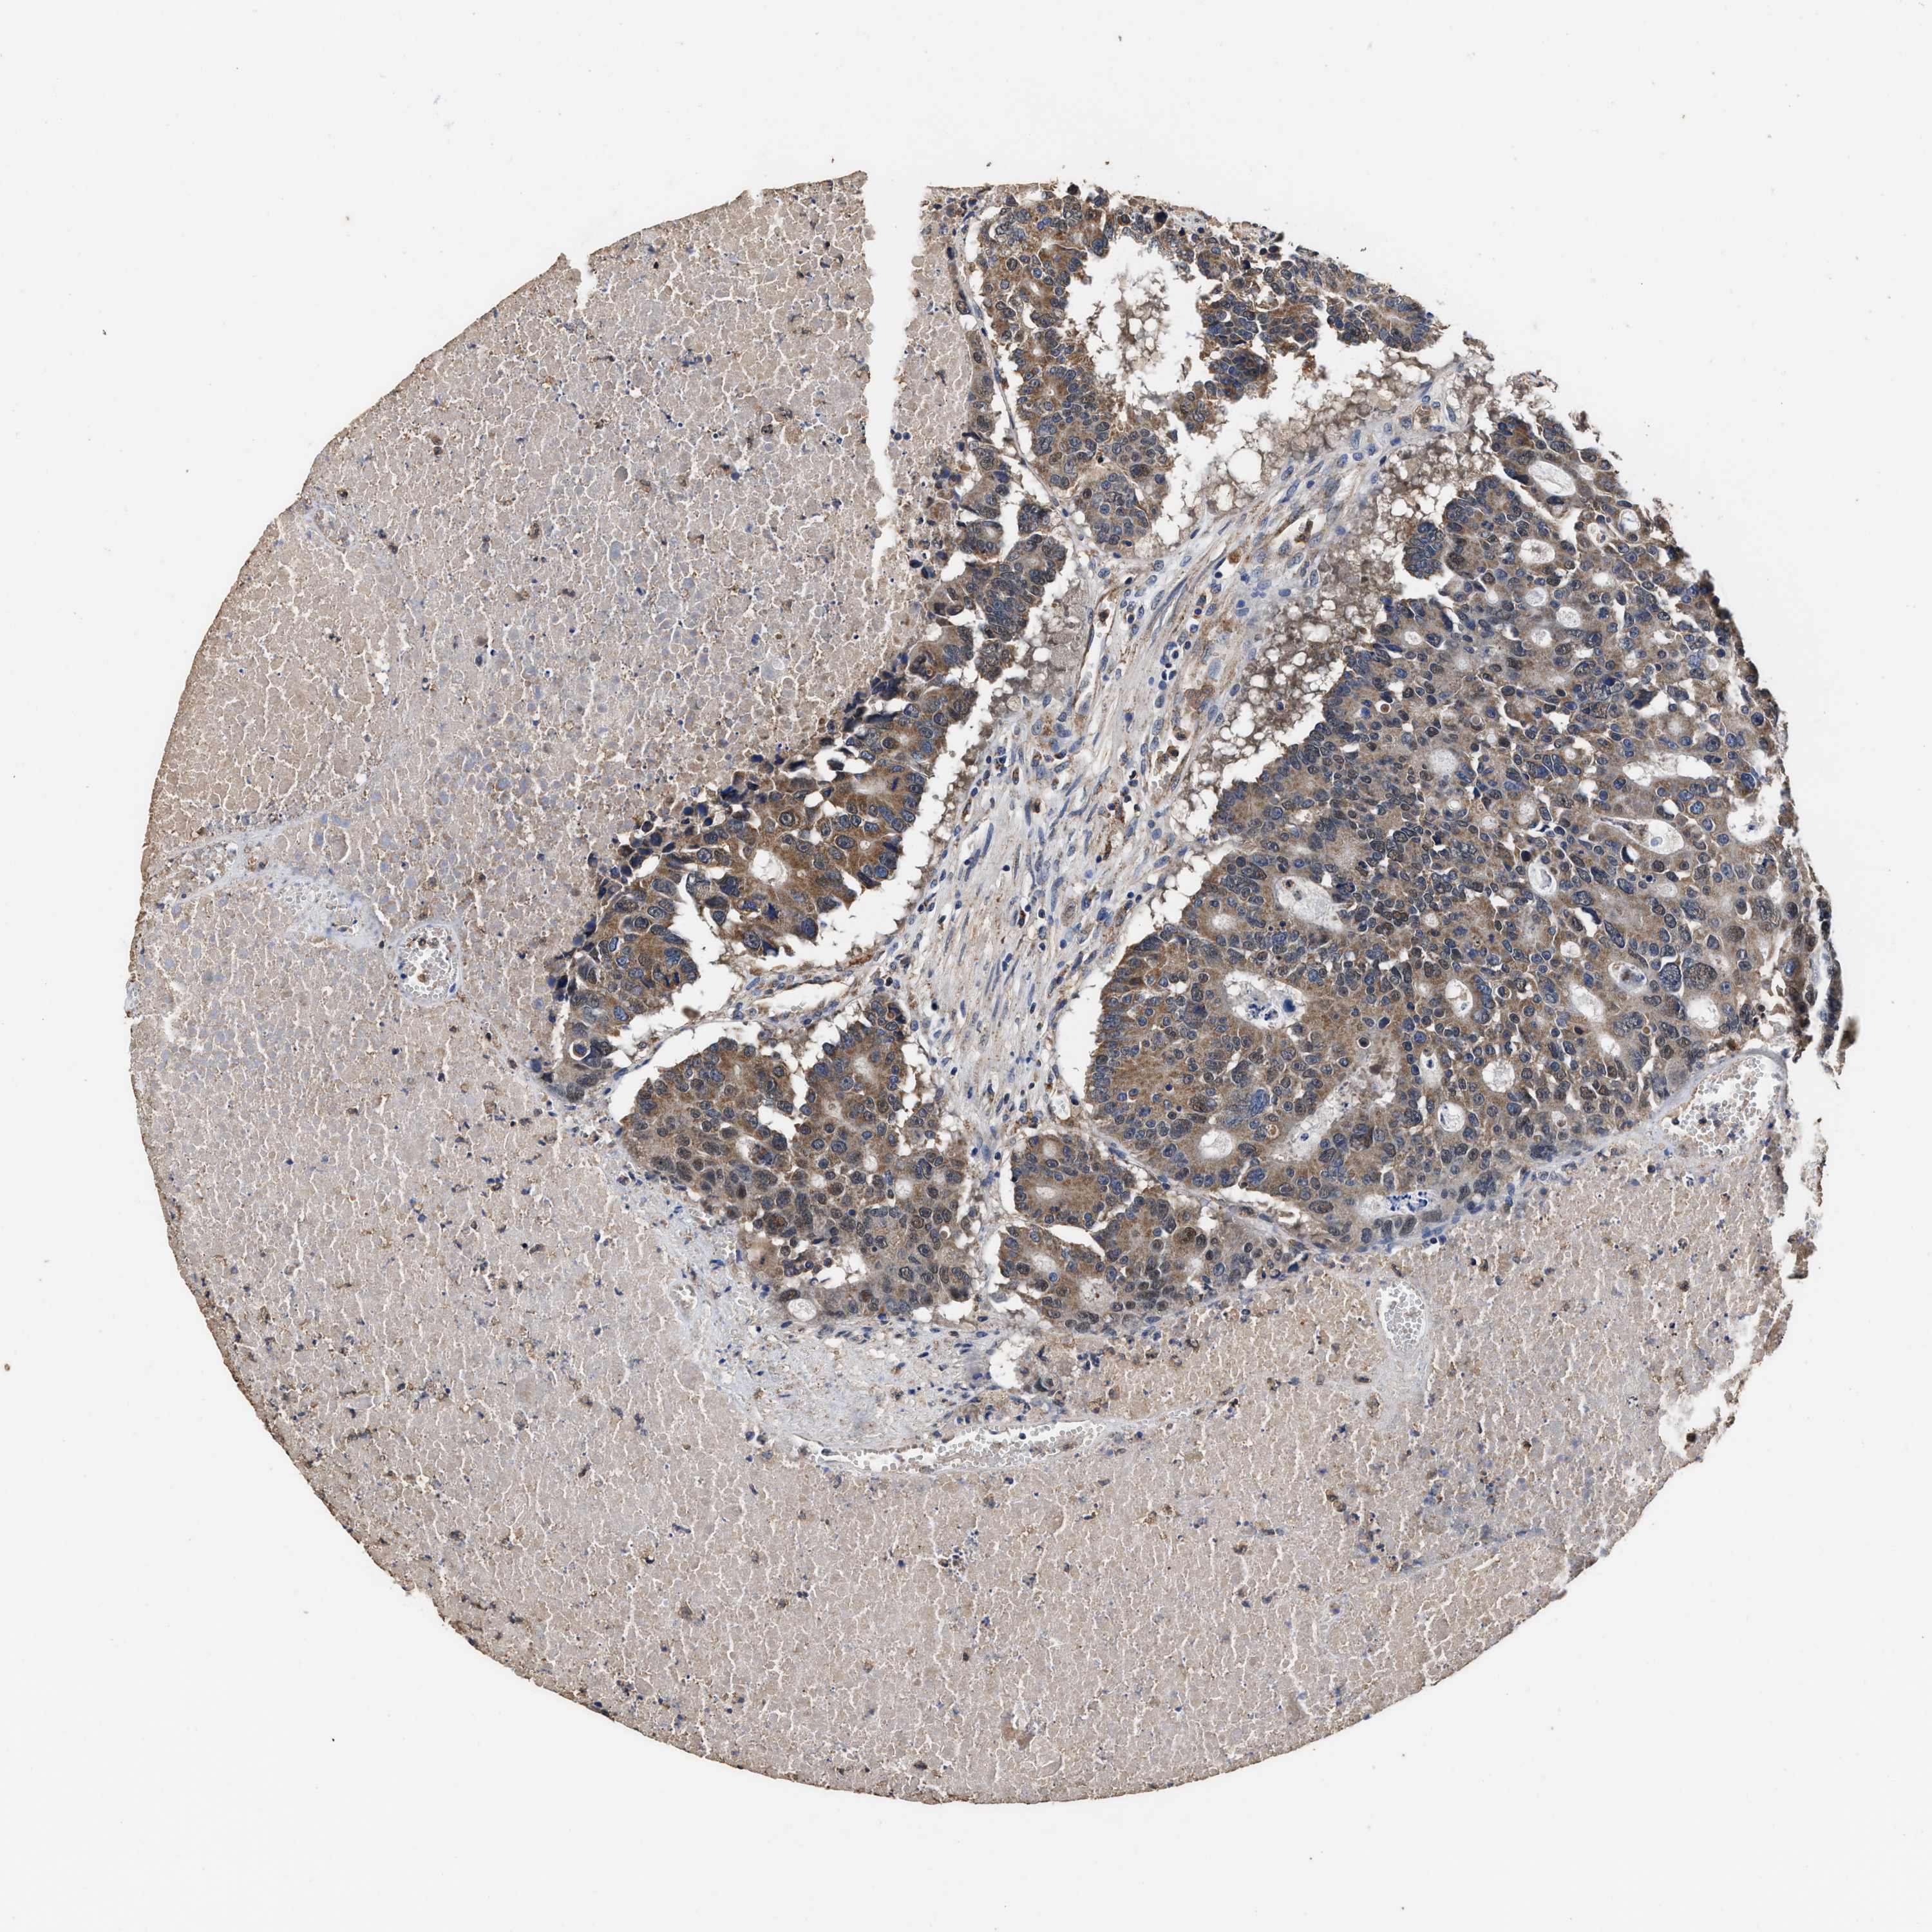

CANCER COLORECTAL CANCER Show tissue menu

Colorectal cancer

Human cancer

Colon adenocarcinoma